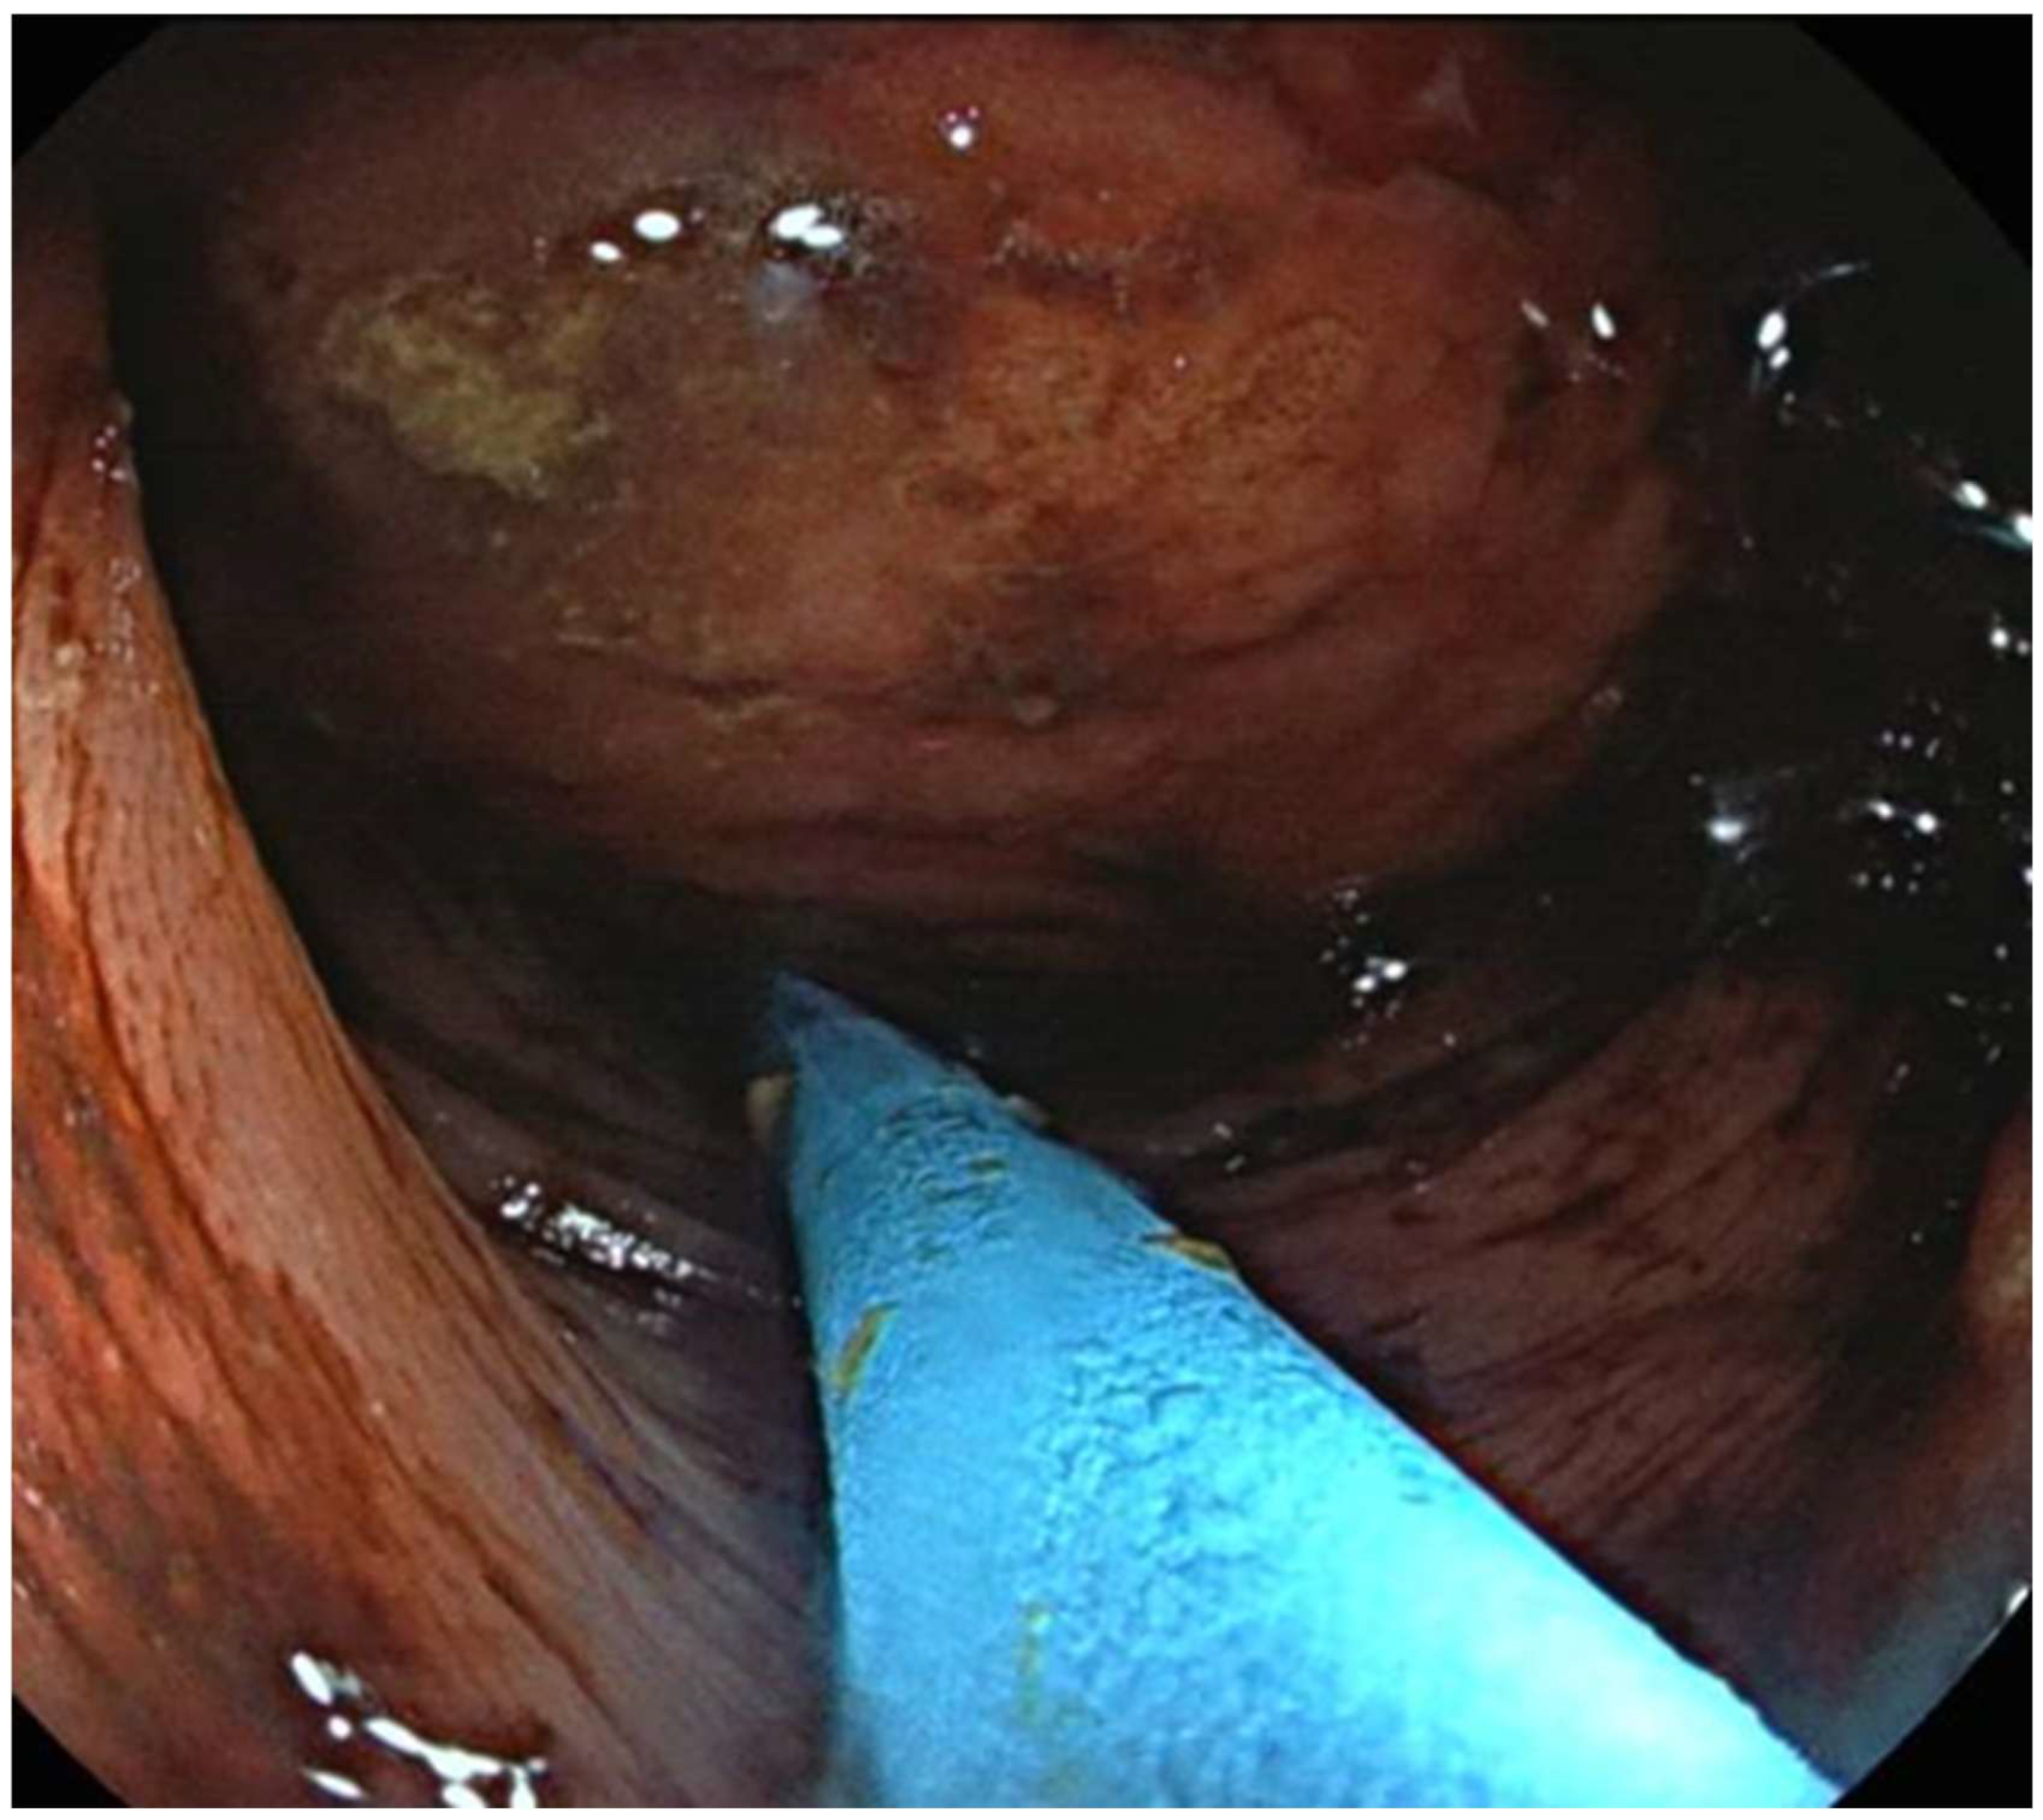

2.4. Endoscopic Techniques